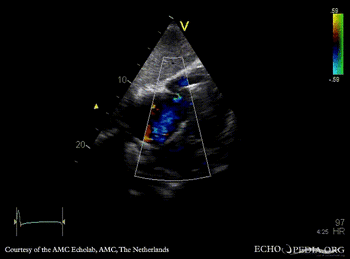

A4CH with Color Doppler: severe tricuspid regurgitation